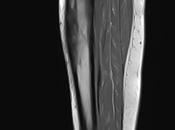

Desgarro muscular de la cabeza larga del bíceps femoral

Motivo de estudio: Revisión por antecedente de desgarre, dolor femoral (datos proporcionados por paciente).Técnica: En resonador de 1. Leer el resto